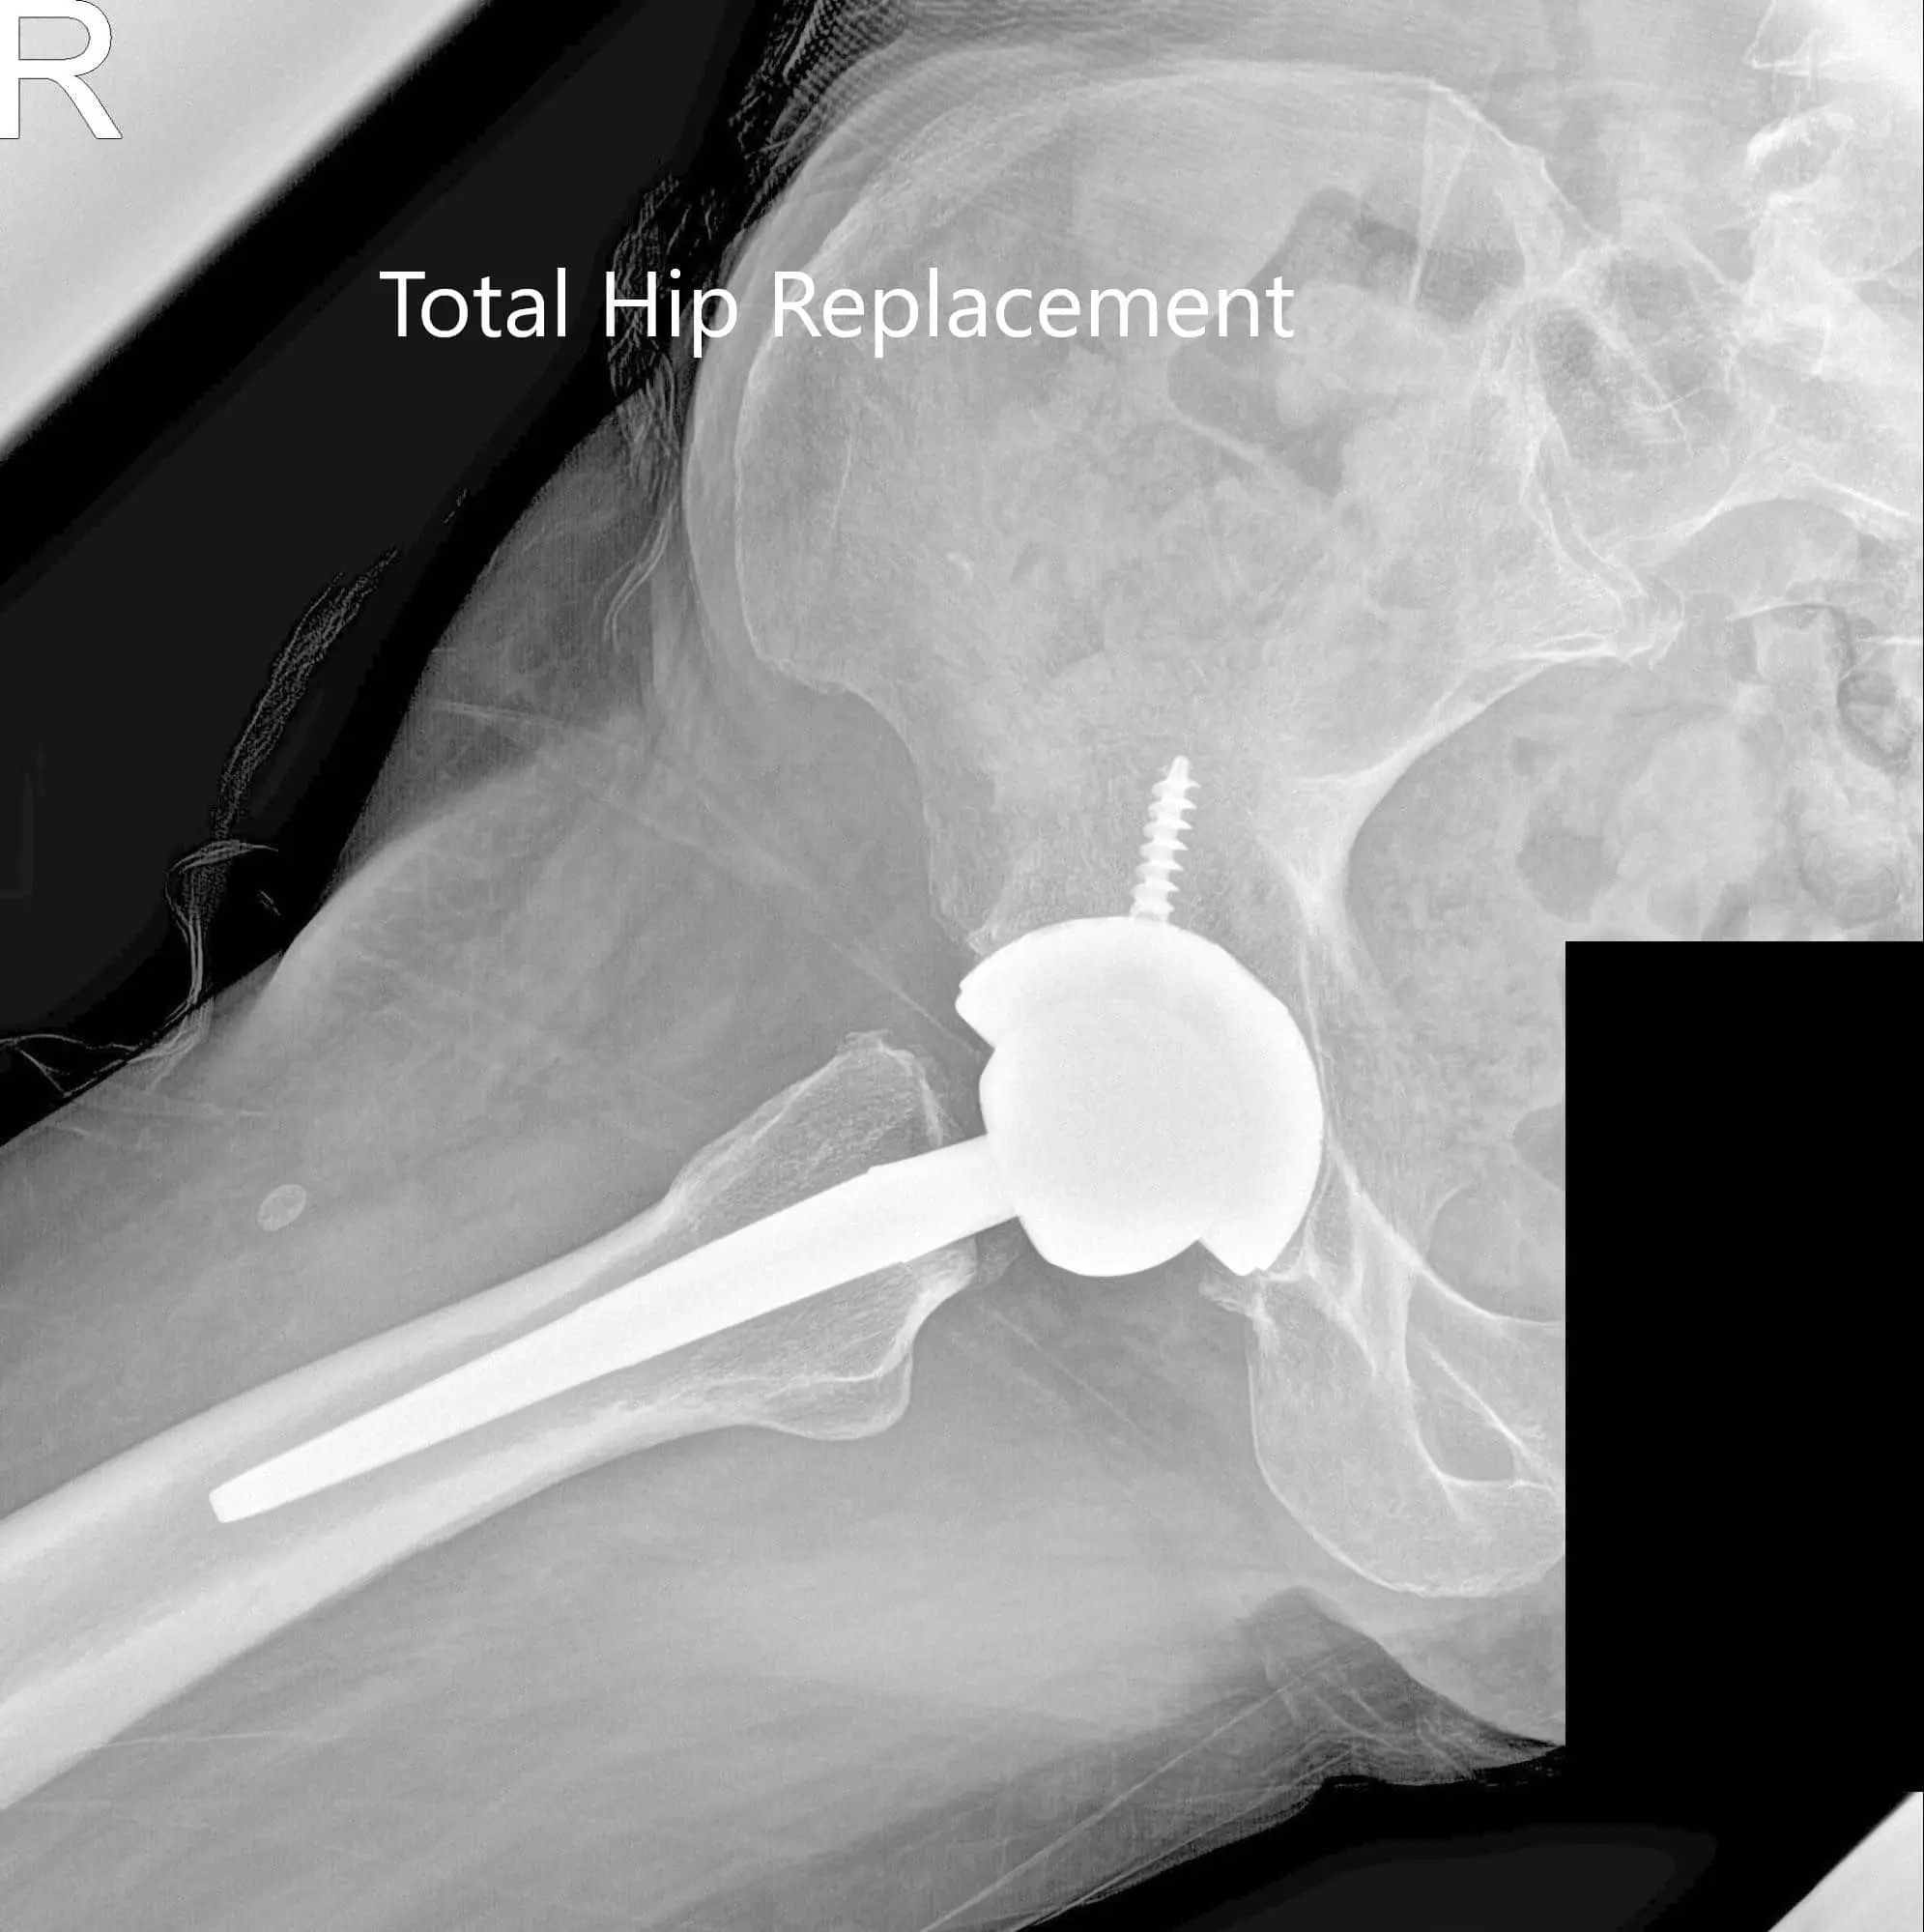

Postoperative X-ray showing the AP and lateral views of the right hip.